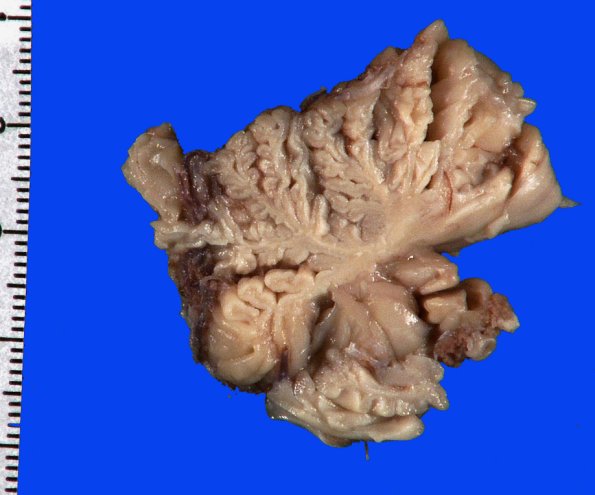

The vermis was particularly atrophic in all areas.